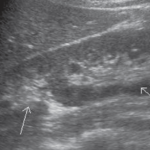

3-Duplex kidney

هذا مصطلح واسع يشمل عدة متغيرات منها وجود كليتين ملتصقات ببعض أو وجود two collecting systems في كلية واحدة. وهذه أيضا يوجد بها متغيرات أخرى من ناحية وجود حالب واحد أو حالبين ووجود شريان واحد أو اثنين.

يوجد هذا المتغير في قرابة ١٠٪ من الناس الطبيعيين. ويجب على الأخصائي التأكد من عدم توسع الحالبين وأيضا عدم وجود انسداد في أحد collecting systems وتحديدا العلوي.